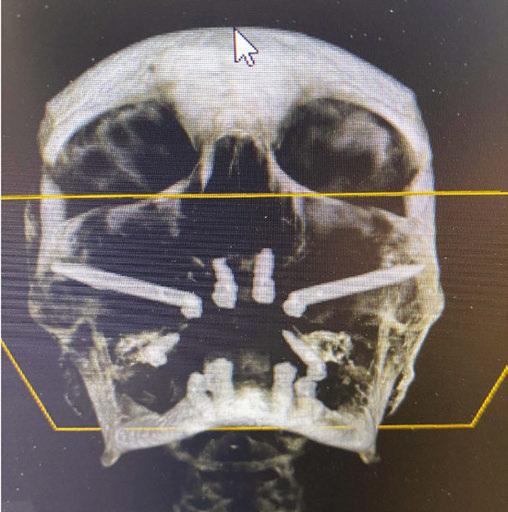

Treatment of severely atrophic maxillae often requires highly advanced procedures such as quad-zygomatic implants1-3 (Figure 1) or customized subperiosteal implants (Figure 2).4,5 Quad-zygomatic implant treatment has a long history of success, but requires significant surgical expertise due to limited malar bone availability and propinquity to anatomic structures such as the orbit and infraorbital nerve.6 Customized subperiosteal implants, on the other hand, are a promising new treatment option but have limited long-term follow-up data and significant expense.7 Transnasal dental implants have recently been introduced as another option for treatment of severely atrophic maxillae, specifically as an alternative to quad-zygomatic implant placement (Figure 3).8 Transnasal implants may serve as a replacement for anterosuperior zygomatic implants as they tangentially traverse the interior lateral nasal wall and achieve high insertion torque via 3 mm-5 mm of apical engagement in the confluence of the inferior concha, lateral nasal wall, and frontal process of the maxilla (Figure 4).8-16

3 (left): 3-dimensional CBCT rendering of patient treated with transnasal dental implants as an alternative to quad-zygomatic implant treatment. Figure 4 (right): Intrasurgical photo of transnasal dental implant traversing the nasal cavity and engaging the base of the inferior concha

Figure 1 (left): 3-dimensional CBCT rendering of patient treated with quad-zygomatic implants. Figure 2 (right): Example of customized subperiosteal dental implant for treatment of an atrophic maxilla